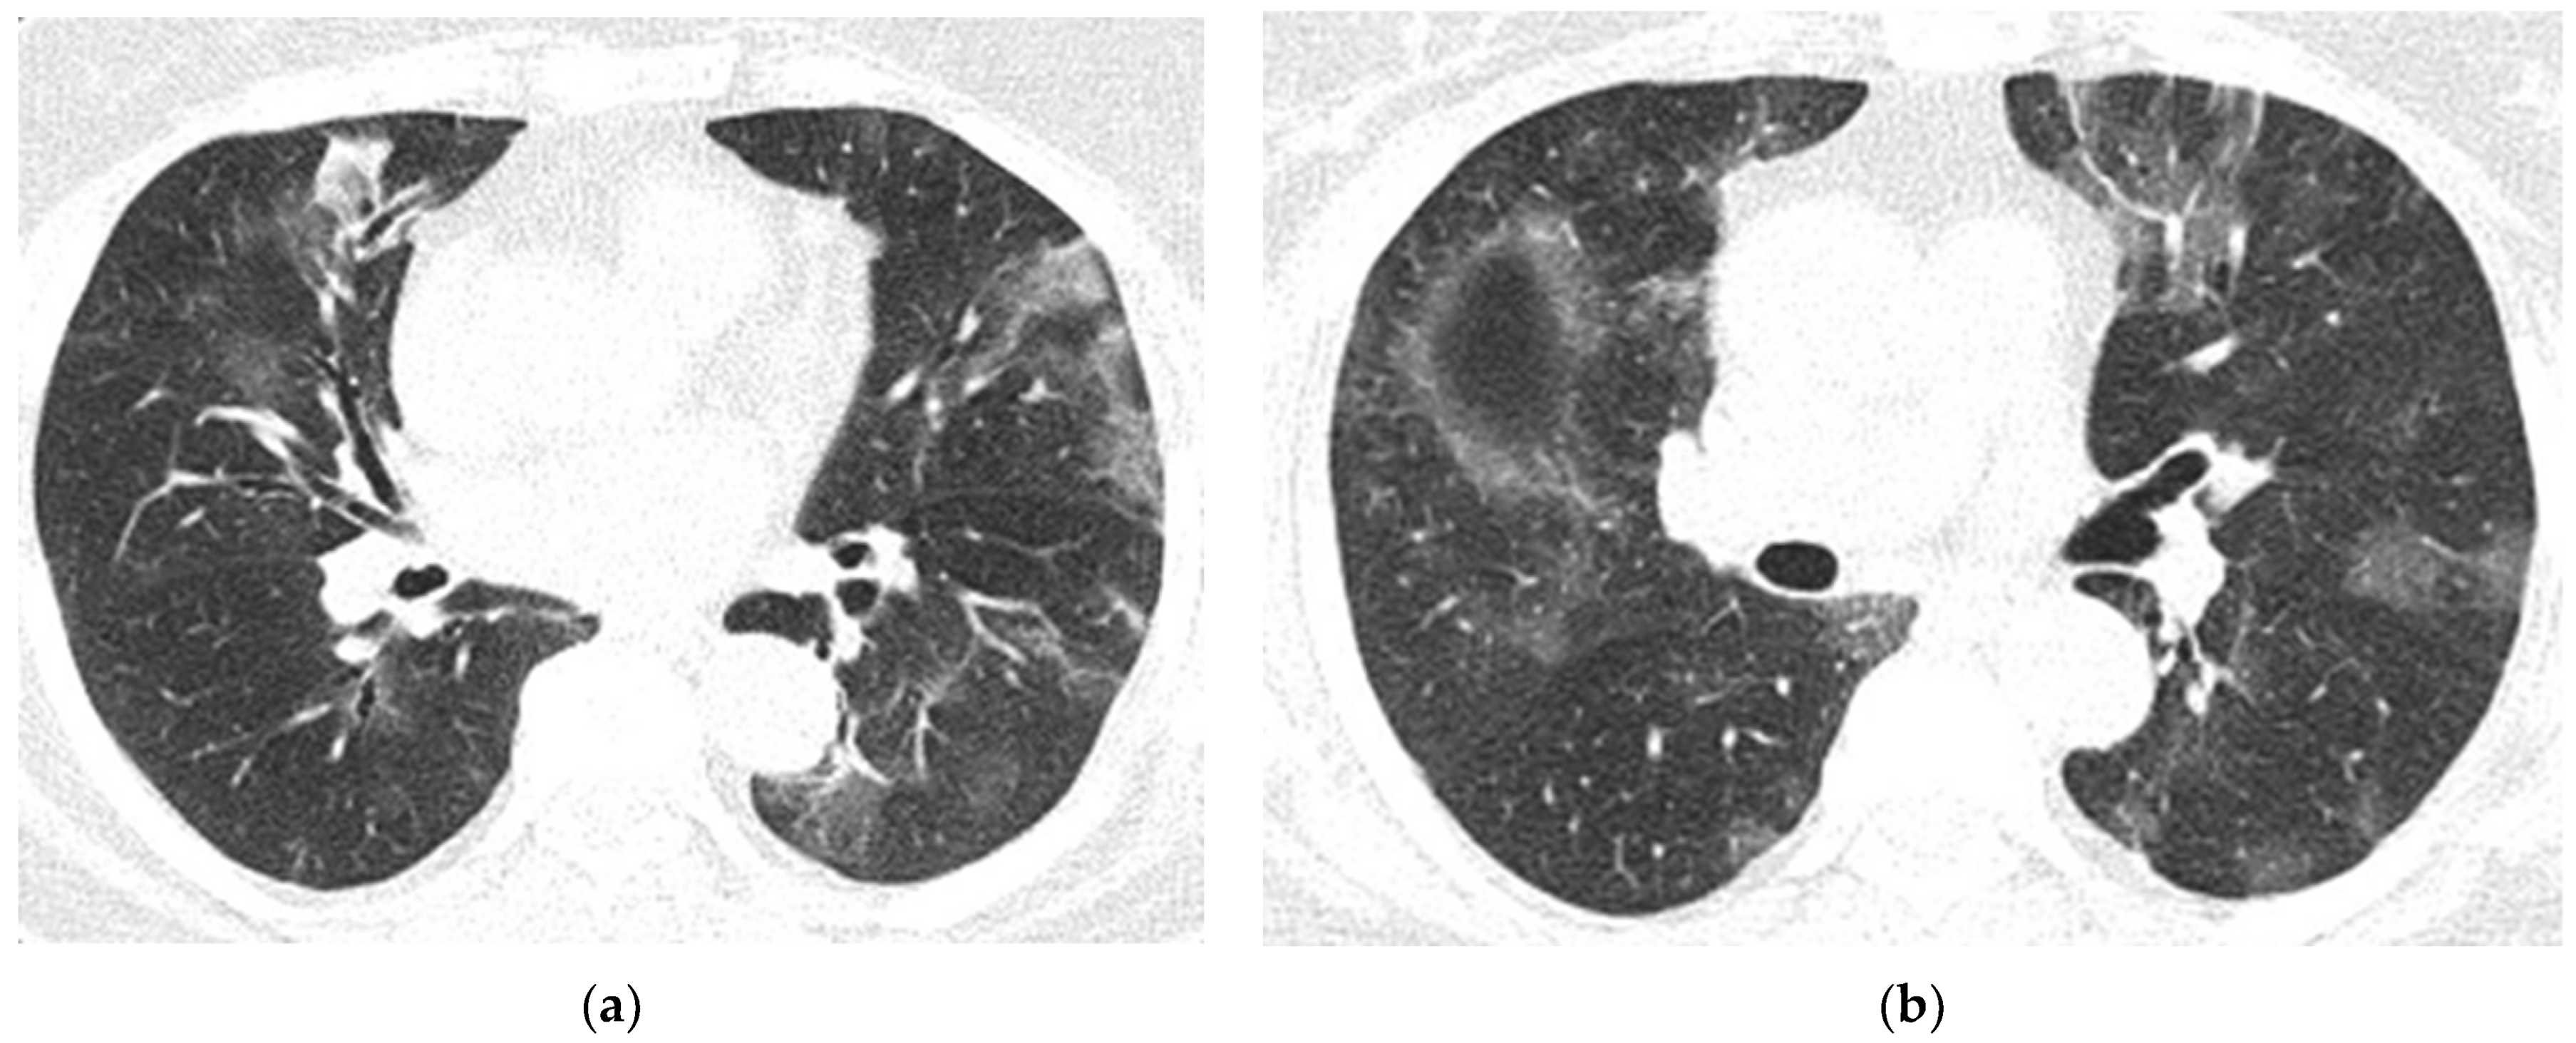

Figure 10. Pulmonary CT images of the Case 10 patient show lesions with a polymorphic aspect, some under the form of inaccurately delimited areas of matt-glass clouding (a,b), and others with increased densities and associated interlobular septal thickness (a), randomly disposed at the level of both pulmonary fields. The tendency was to condensate some lesions from the level of the right anterior basal segment (a). Linear fibrosis outlines with retractile effect on the parietal pleura and on some subsegmental bronchial outlines, which could be highlighted especially at the inferior lingual level and at the level of the basal pyramid, bilaterally (a,b). In conclusion, fiber–alveolar–interstitial modifications are compatible with lesions of SARS-CoV-2 type in various phases of evolution, with a severity score of 13 (8 right lung, 5 left lung), determinable in moderate impairment.